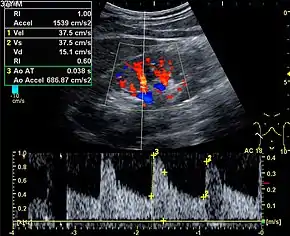

%252C_diastolic_velocity_(Vd)%252C_acceleration_time_(AoAT)%252C_systolic_acceleration_(Ao_Accel)_and_resistive_index_(RI)_of_normal_kidney.jpg.webp)

Doppler ultrasonography is widely used in renal ultrasonography. Renal vessels are easily depicted by the color Doppler technique in order to evaluate perfusion. Applying spectral Doppler to the renal artery and selected interlobular arteries, peak systolic velocities, resistive index, and acceleration curves can be estimated (Figure 4) (e.g., peak systolic velocity of the renal artery above 180 cm/s is a predictor of renal artery stenosis of more than 60%, and a resistive index, which is a calculated from peak systolic and end systolic velocity, above 0.70 is indicative of abnormal renovascular resistance).[12]